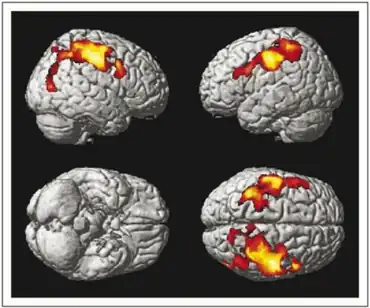

Expanded Disability Status Scale (p < 0.05 corrected for multiple comparisons at cluster level, i.e. t score >3.16) in individuals with relapsing–remitting multiple sclerosis | |